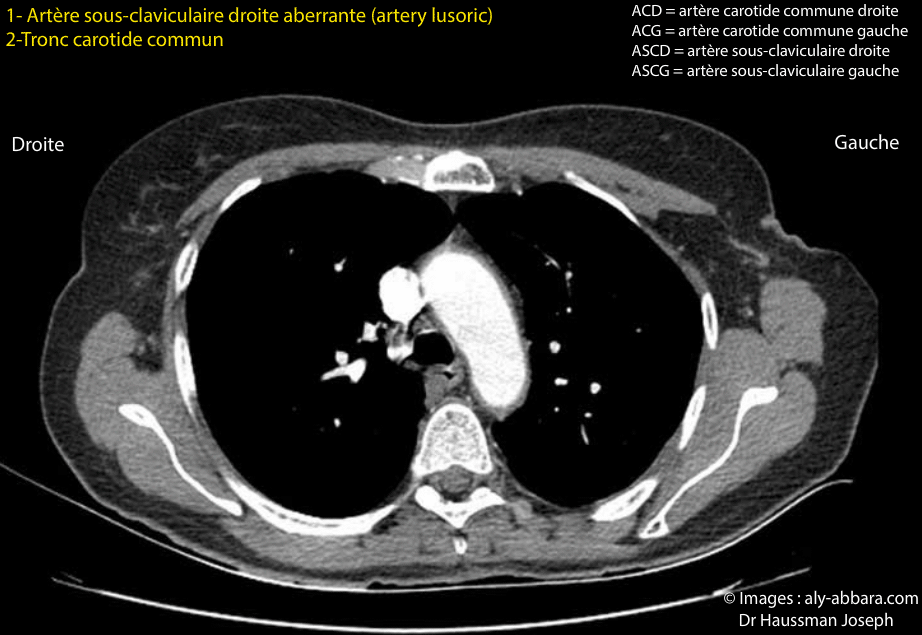

- Dans le cas présent, de la crosse de l'aorte naissent successivement trois vaisseaux artériels :

- 1- un tronc artériel qui se divise en deux artères :

- l'artère carotide commune droite ;

- l'artère carotide commune gauche.

Ce tronc est donc bicarotidien.

- 2- l'artère sous-claviculaire gauche ;

- 3- l'artère sous-claviculaire aberrante droite (ou l'artère lusoric -arteria lusoria) qui se dirige vers le haut, l'arrière et à droite puis passe derrière l'œsophage et enfin, se dirige vers la droite et en avant pour atteindre la région sous-claviculaire droite et le membre supérieure homolatérale.